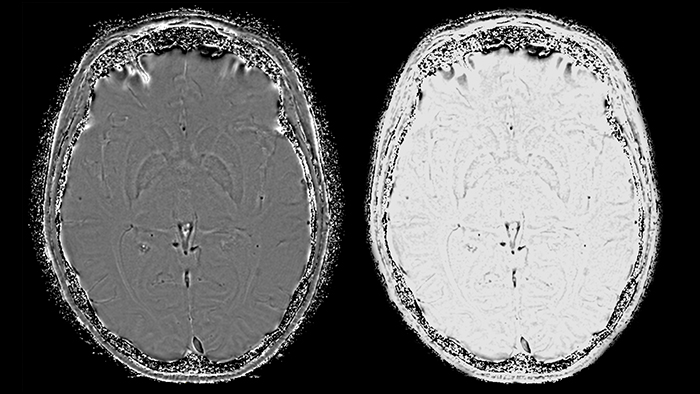

Магнитно-резонансная томография (МРТ) играет важную роль в диагностике неврологических заболеваний. Классические последовательности, применяемые в клинической практике, отражают такие ключевые параметры тканей, как: времена релаксации T1, T2 и T2*, измеряемый коэффициент диффузии и протонную плотность. Широко применяются последовательности, взвешенные по T1 и T2, инверсия-восстановление с подавлением воды (FLAIR) и диффузионная МРТ (рис. 1).

Умножение этой маски на магнитудное изображение никак не повлияет на области с положительной накопленной фазой, но повысит контрастность областей с повышенным содержанием парамагнитного железа. Конечный результат последовательности SWIp – SWI- и отфильтрованное фазовое изображение (рис. 6), обладающие уникальным контрастом, при этом первое отражает как локальные изменения магнитной восприимчивости тканей, так и значение амплитуды МР-сигнала. Таким образом, принципиальное преимущество метода SWIp по отношению к T2*-взвешенным изображениям - использование фазовых данных для повышения первоначального контраста магнитудных изображений. Это обуславливает более высокую диагностическую ценность этой методики по сравнению с T2* последовательностями [9].